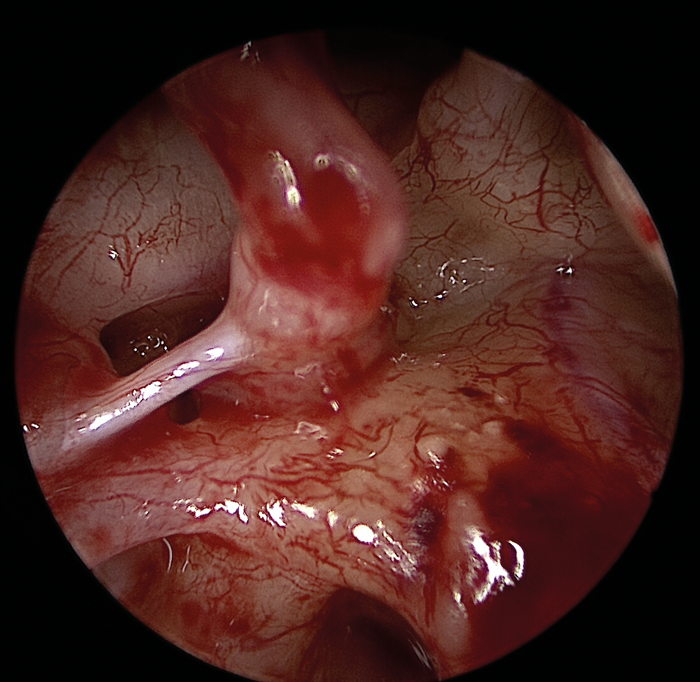

The greatest benefit of the endoscope lies in exposing previously hidden areas or blind spots such as the retrotympanum, hypotympanum, anterior mesotypanum, epitympanum and antrum (Figure 4).

Figure 4 (Top, middle and bottom): Endoscopic view of the middle ear with an intact ossicular chain.